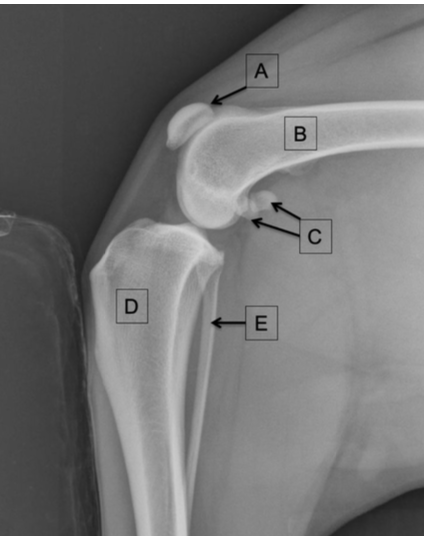

Q

Label the structures

A

A = patellar tendon

B = menisci

C = infrapatellar fat pad

D = gastrocnemius m.

E = popliteal lymph node

How well did you know this?